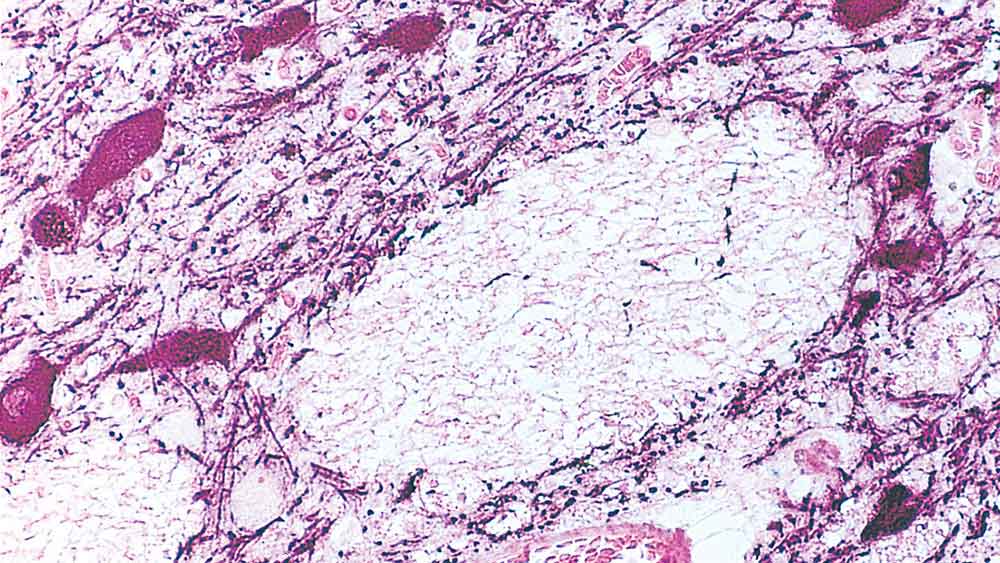

IHC-P analysis of human midbrain using GTX01922 Tyrosine Hydroxylase antibody [1B5]. Note cytoplasmic staining of catecholaminergic cells and their processes.